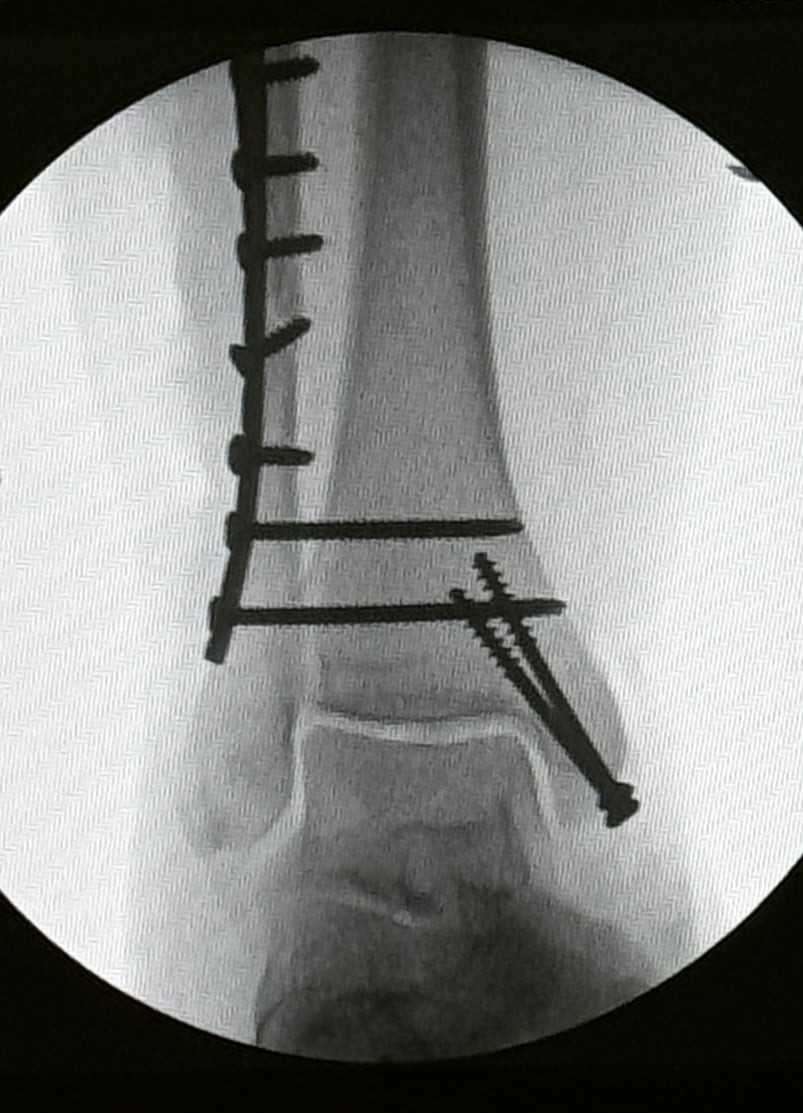

Above: my metalwork

I think it was around 5.30pm that I came round in recovery with 9 screws and a metal plate in my leg. The pain - crikey. It was at it’s worst. And I was also STARVING! Every time I wailed with pain I heard a doctor say “give her more x”, “another dose of y” - apart from the moaning and groaning of pain I was totally consumed with how hungry I was! I was saying to the doctors “is it safe for me to have all this medication on an empty stomach?!” 😂 I just couldn’t stop talking about it, I kept asking the nurses if there was any scrap of food about that I could eat, a couple of biscuits perhaps? They just kept saying they didn’t have anything - I mean why would they! Recovery is for drugs it’s not a restaurant! However, after me going on and on a kind nurse said that someone had bought in doughnuts today for a birthday and I could have her doughnut! “I can’t take your doughnut!” I wailed! But she insisted, so I did - it was the best doughnut I’ve ever had.